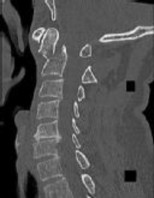

Figures 1 and 2 are CT scans obtained from a 68-year-old man who has had

progressive neck pain and stiffness, worsening gait imbalance, upper extremity weakness, early muscle fatigue, difficulty with fine motor control, and difficulty with activities of daily living over the past few years. On physical examination, he has a wide based stiff legged gait, generalized upper extremity weakness, dense sensory loss in the upper and lower extremities, and markedly brisk reflexes. What is the most appropriate treatment for this patient?

4. Posterior cervical laminoplasties from C3-6 Discussions: D

This patient has progressive myelopathy secondary to ossification of the posterior longitudinal ligament. Diagnostic imaging reveals multilevel cervical cord compression from C4-6. The patient has maintained reasonable cervical lordosis. A posterior procedure such as multilevel laminoplasty

decompresses the spine, is motion preserving, and has a low complication rate. Observation and cervical epidural injections are not viable options in patients with progressive myelopathy. Anterior cervical decompression, including corpectomy, is an option; however, anterior procedures have an increased risk of complications such as dural tear or cerebrospinal fluid leak. The axial CT image shows a "double layer" sign, which is consistent with dural ossification and increases the risk of dural injury with anterior decompression